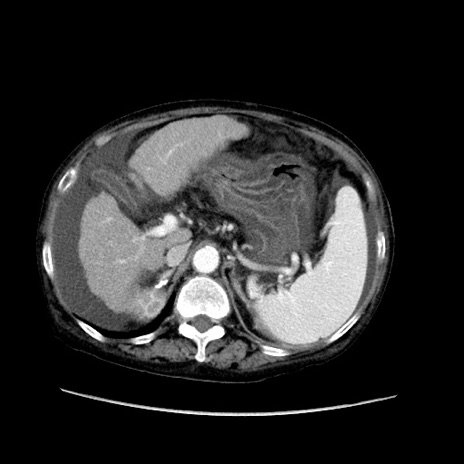

症例31(横断像)

【症例】80歳代 女性

【主訴】腹部膨満感

【現病歴】他院にて肝硬変にてフォロー中。1週間前から便秘、腹部膨満感、臍部腫瘤あり受診となる。

【既往歴】肝硬変

【身体所見】腹部膨隆あり、皮膚変化なし、疼痛なし。

【データ】WBC 4600、CRP 0.25